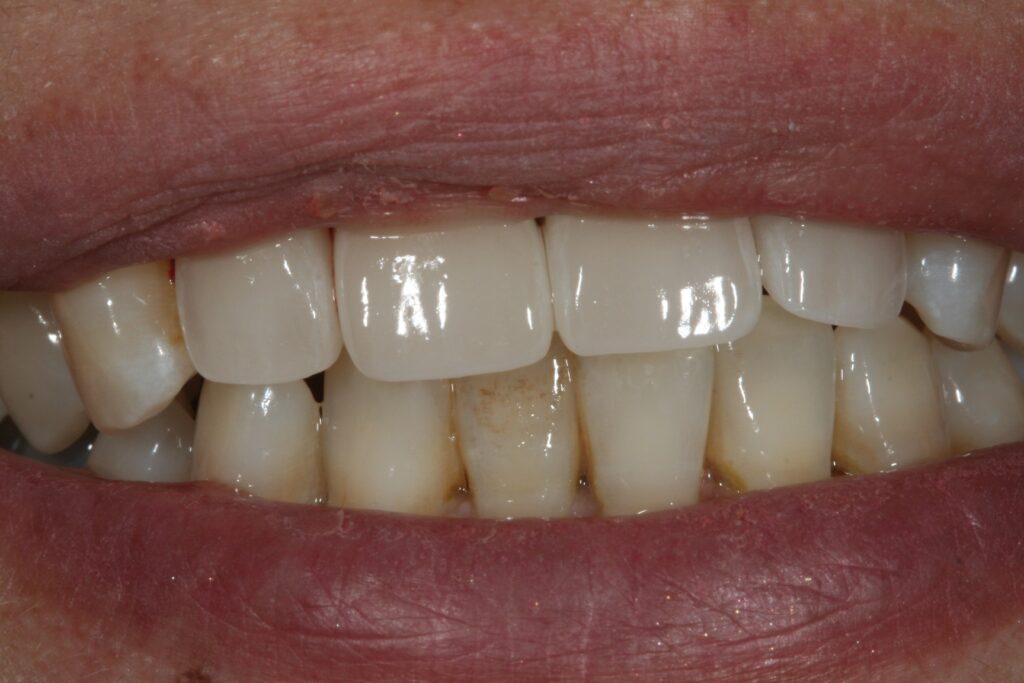

審美治療 2015.09.26 症例紹介 10年以上前から前歯の見かけが気になっておられました。1回目:カウンセリング2回目:治療、型取り、仮の歯3回目:取り付けて終了 でした。 症例紹介 都市伝説、、、、、前の記事 歯石とは?次の記事